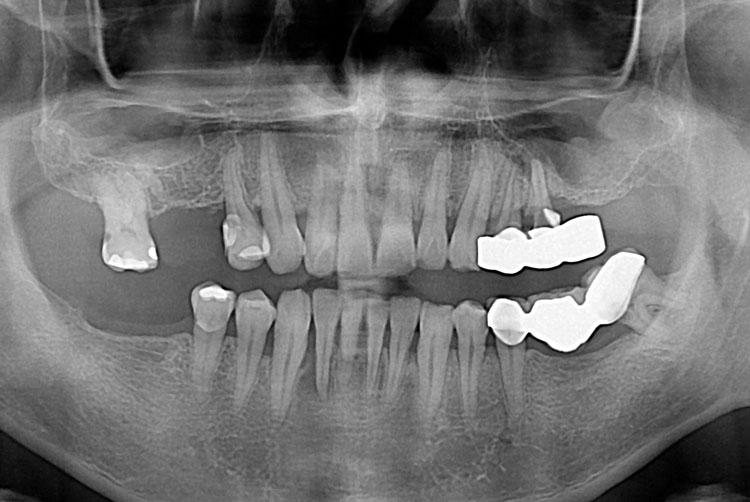

[임플란트] 임플란트

치료전 : 2017-07-13

세종치과는 많은 환자와 다양한 케이스를 바탕으로 항상 편안한 임플란트 수술을 제공하고자 노력하고,

오래동안 튼튼히 쓸 수 있는 임플란트 수술을 가장 큰 목표로 삼고 있습니다.